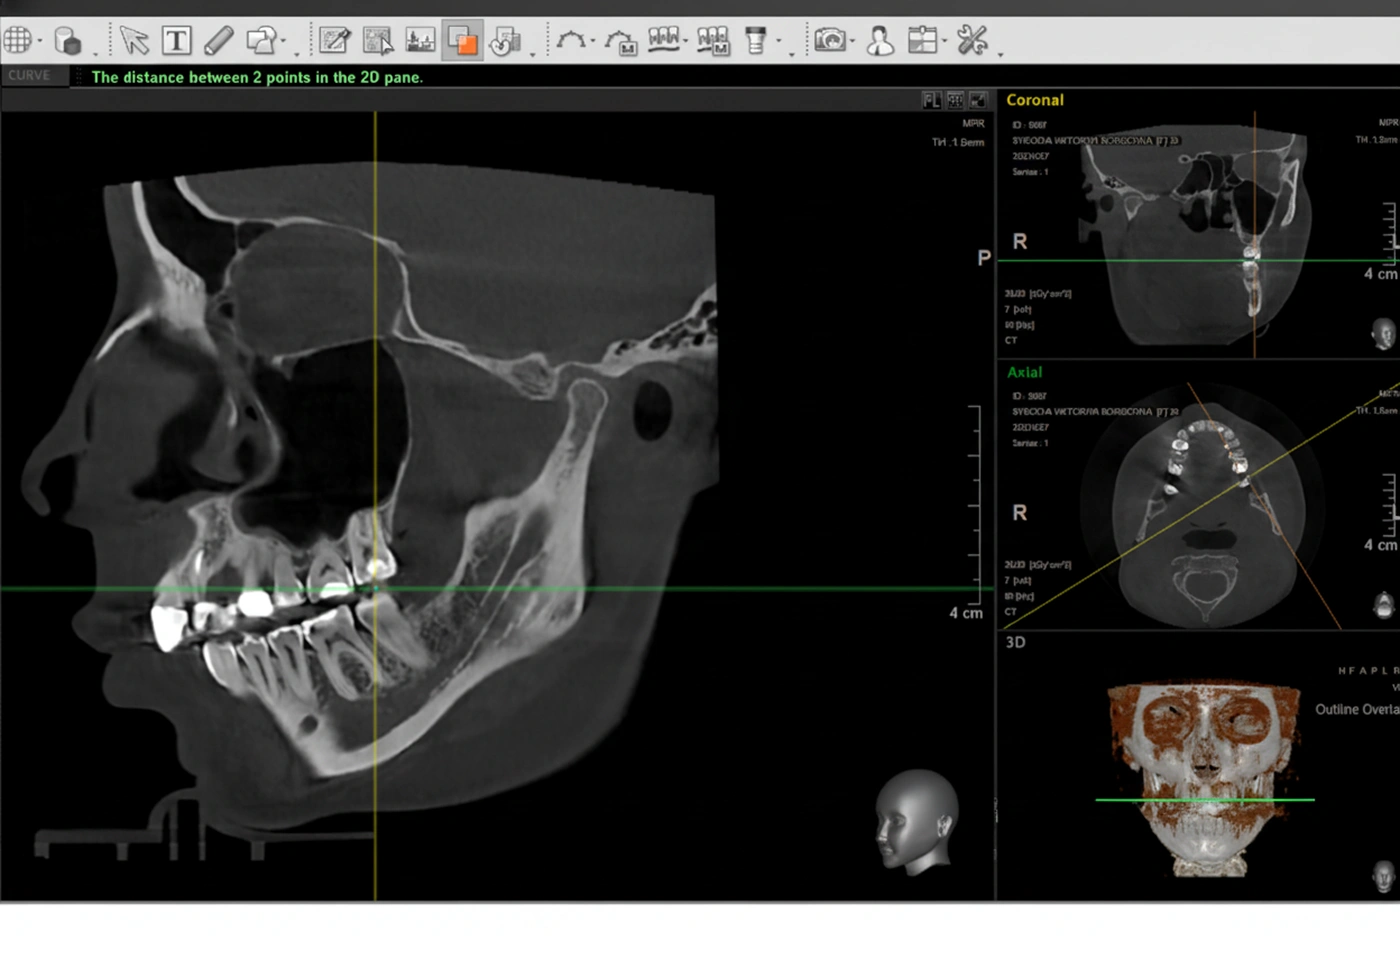

Перед началом лечения я провожу часовую первичную консультацию. Для этой встречи вам необходимо сделать «МРТ ВНЧС» и «КЛКТ двух челюстей с захватом ВНЧС в привычном прикусе».

Во время консультации мы смотрим и анализируем ваши исследования. Я подробно объясняю строение ВНЧС, показываю все причинные факторы вашей проблемы, отвечаю на все вопросы «Почему?»